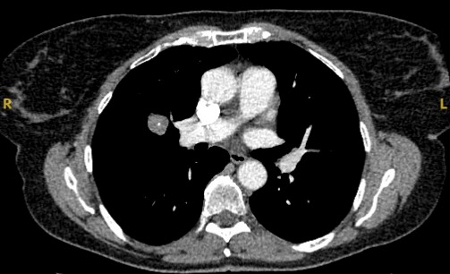

[Figure caption and citation for the preceding image starts]: Corte de tomografia computadorizada (TC) com configuração de tecidos moles, mostrando hamartoma de pulmão direito, como achado incidental em paciente assintomático. Observe a calcificação central e vários pequenos pontos de gordura dentro do nódulo. Este nódulo permaneceu estável durante um período de 12 anos, não tendo sido necessária nenhuma intervençãoDo acervo de Dr. George Tsaknis, MD, PhD, FRCP (Londres), MRQA, MAcadMEd, PGCert; usado com permissão [Citation ends].